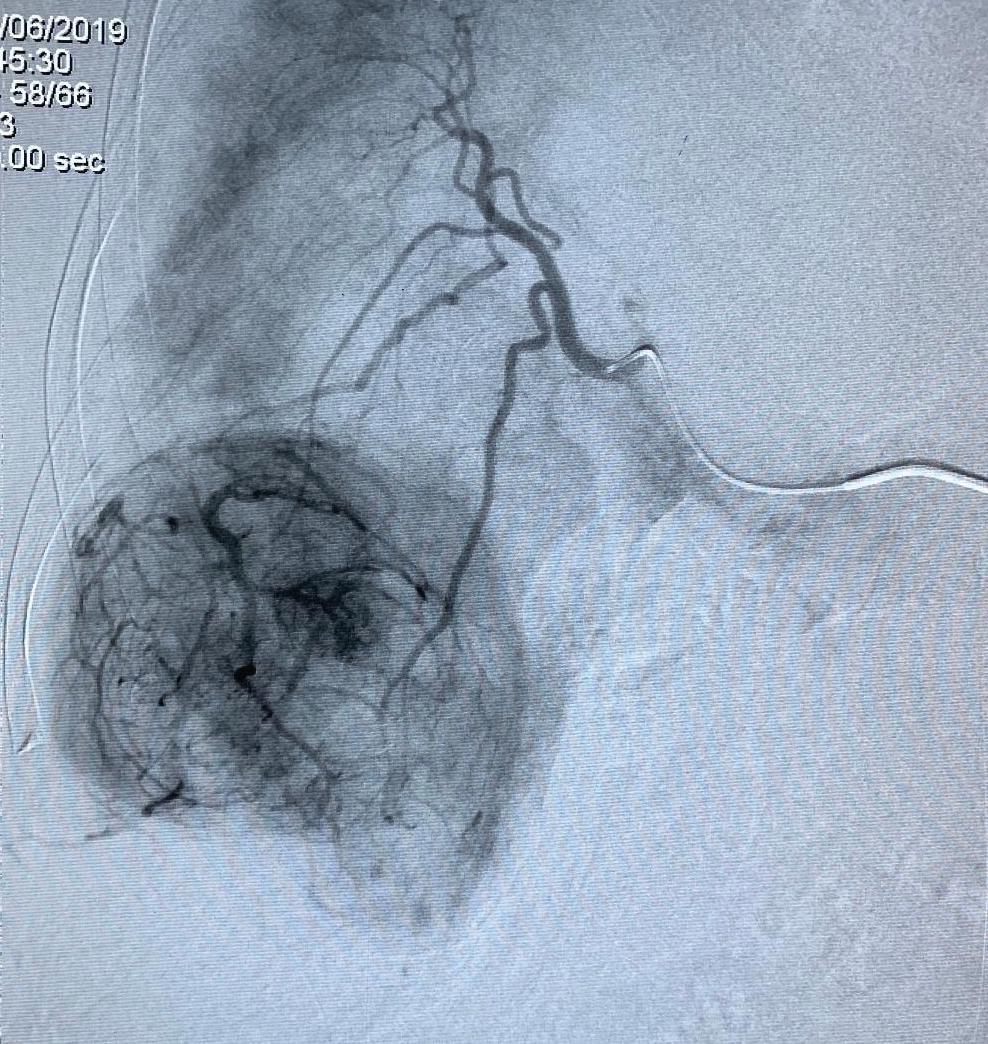

INTERVENCIONAL

Patología pelviana femenina y manejo intervencional. Dr. Nicolás Martínez

Manejo malformaciones vasculares. Dr. Gian Paolo Zamboni

Manejo estenosis biliares. Dr. Nicolás Zugbe

Acceso endoscópico biliar percutáneo. Dr. Marcos Tapia

Técnicas de Ablacíon (Desde la alcoholización a la electroporación). Dr. Marcelo Klein

Coffee Break: Exhibición comercial y pósters

Ablación del cuello más allá del bocio. Dr. José Luis del Cura

Equipo Pert Dr. Diego González

Trombectomía mecánica en el tromboembolimo pulmonar. Dr. Marcos Tapia

Ablación percutánea cáncer de pulmón. Dr. Eduardo Eyheremendy

Principios diagnóstico y tratamiento fístulas de diálisis. Dr. Eduardo Eyheremendy

Manejo endovascular del TEP, revisión de la evidencia. Dr. David Clemo